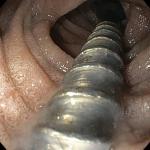

प्रेम सुपर स्पेशलिटी अस्पताल पानीपत की ऐतिहासिक उपलब्धि, 5 वर्षीय बच्चे की बचाई जान

सत्य खबर हरियाणा Great Achievement : प्रेम सुपर स्पेशलिटी अस्पताल बिशन स्वरूप कॉलोनी, पानीपत के गैस्ट्रोएंटरोलॉजी (पाचन तंत्र विशेषज्ञ) विभाग…